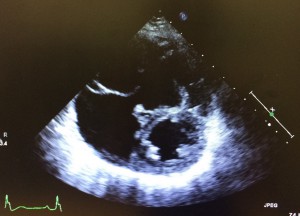

左写真はMICSで行ったコーン手術の術前(上)と術後(下)の心エコー写真です。三尖弁の逆流が減り、巨大だった右室と右房が著明に改善しています。